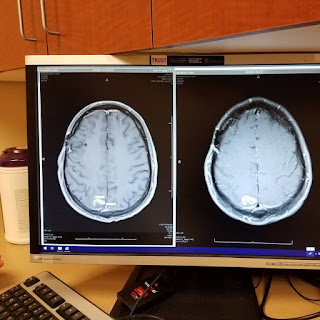

The next day, Thursday the 19th, I had an appointment with my oncologist and an infusion scheduled. We went over my brain MRI images and had great results! Three of the four tumors shrunk! And one got bigger, but it was still weird. Either way, it was good news. Does that mean the tumors will continue to shrink? My radiation oncologist says no, they will likely regrow, but it was decided to only irradiate the one tumor that got larger and to watch the other three. Here are the images (the left side is the most recent image)...

This is the one that got bigger...but it doesn't look much bigger and it's odd shaped.